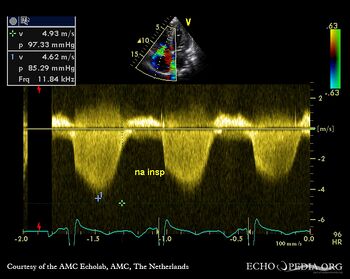

E00440.jpg

A4CH: Color Doppler, severe tricuspid regurgitation Continuous-wave signal of tricuspid regurgitation, increased systolic pulmonary artery pressure